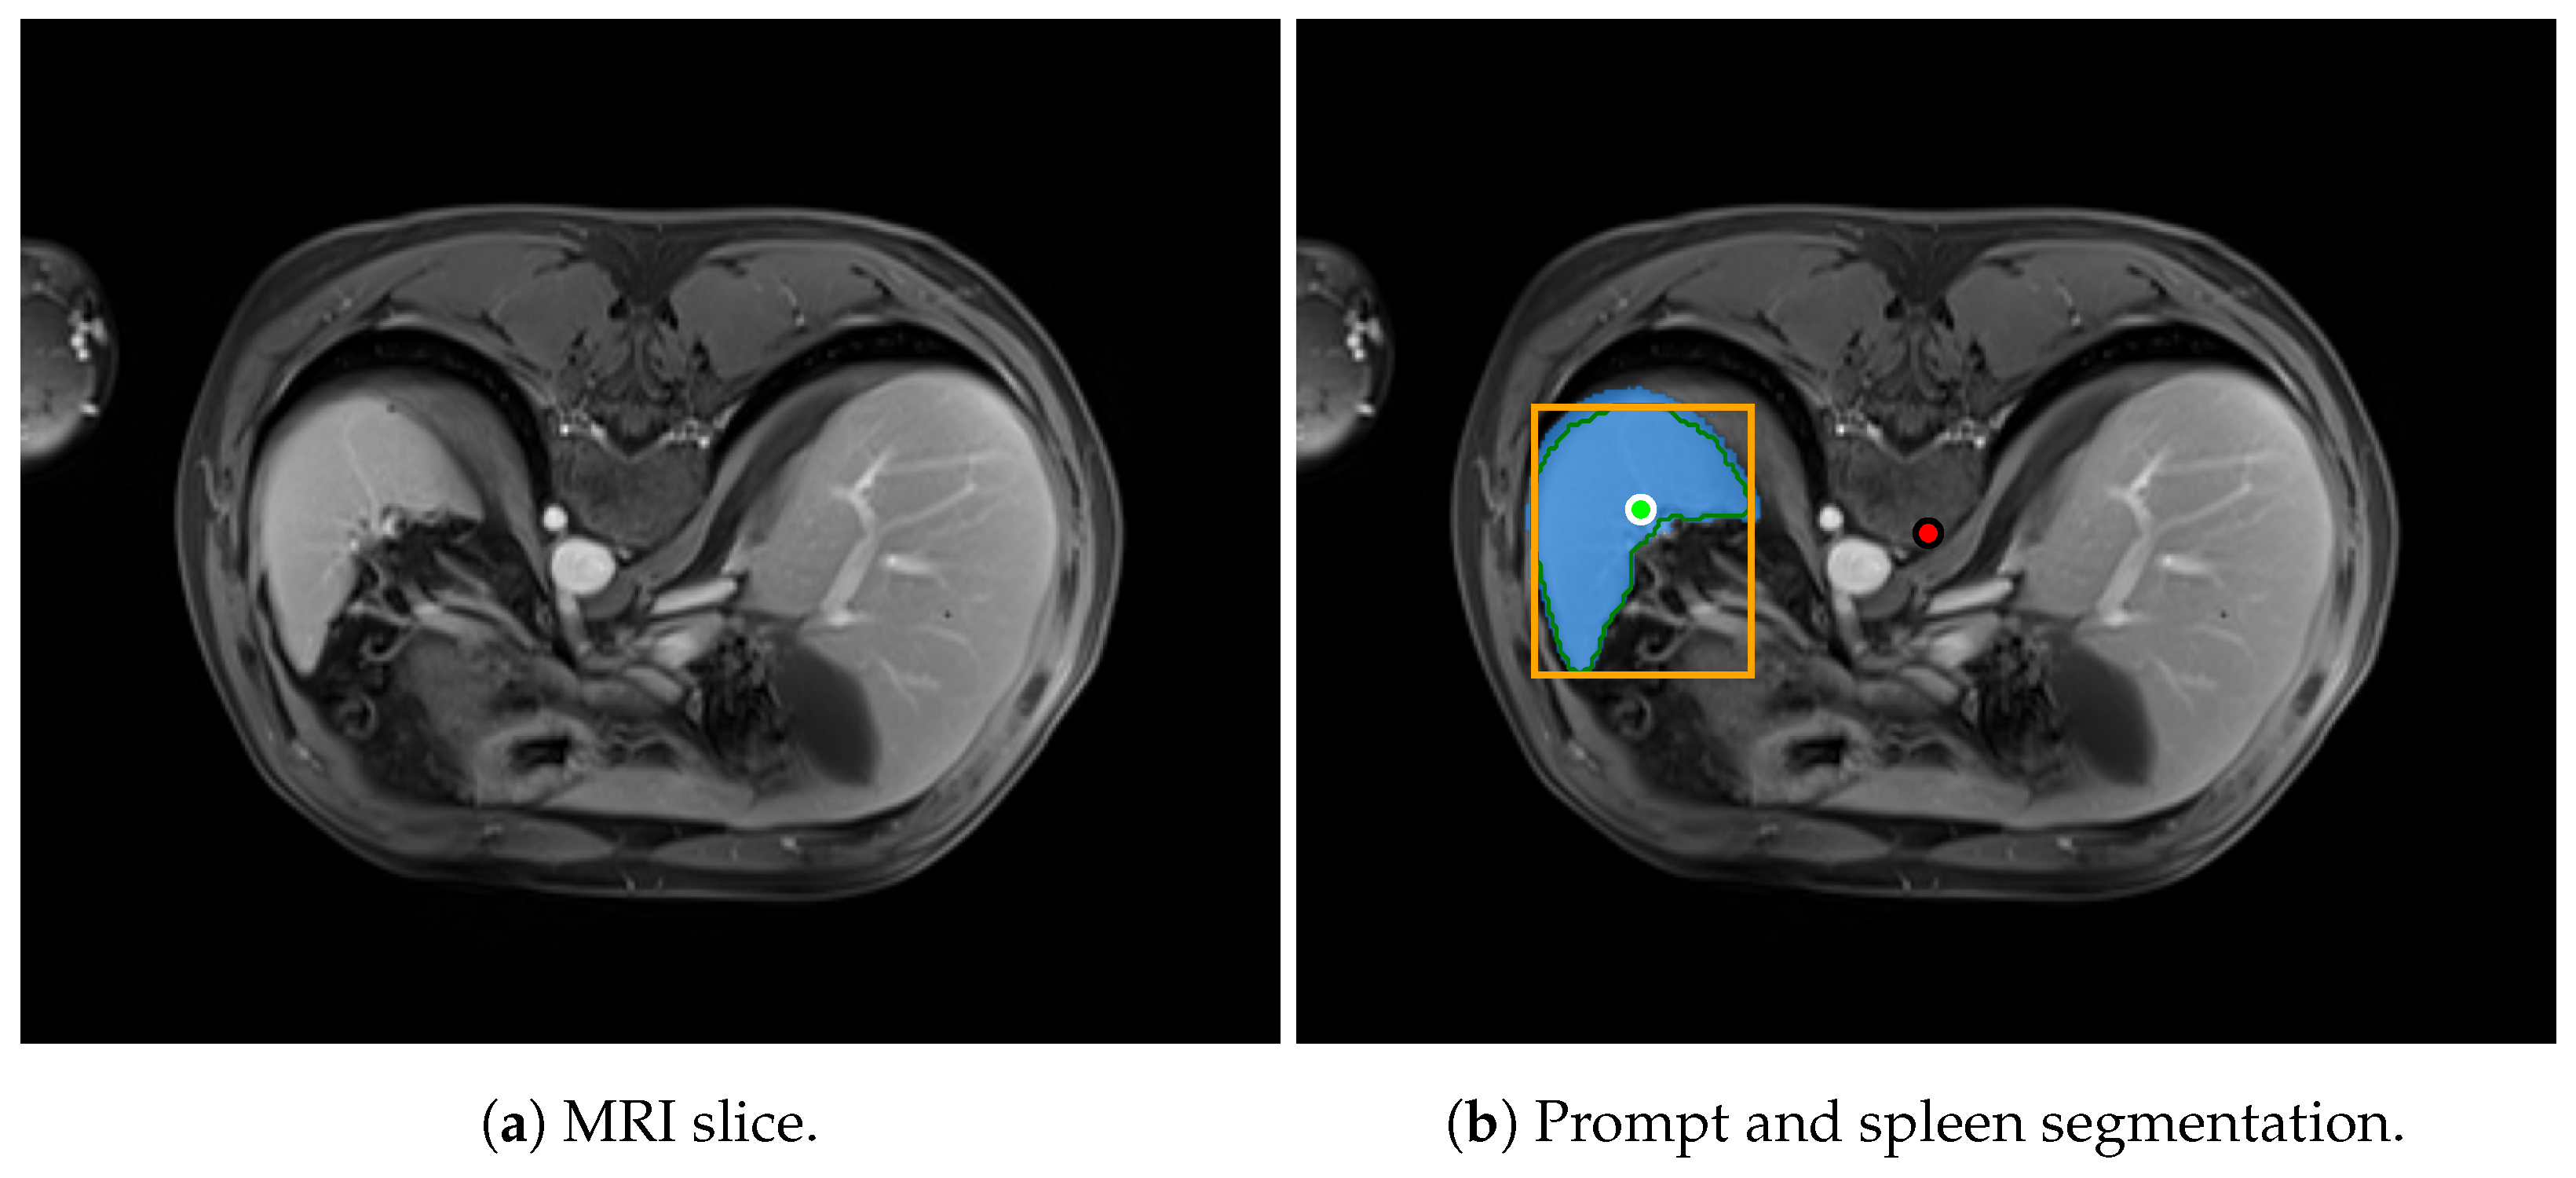

In this study, the selected prompting approach combines minimal point coordinates within a bounding box. This method is intended to simulate an interactive tool where a specialist might begin by drawing a bounding box around the lungs, then marking the areas to be segmented (i.e., the lungs), and finally, indicating parts of the background to be excluded. Figure 1 illustrates two examples of this approach using different CT slices: one from each subset of the selected dataset (Coronacases and Radiopaedia) and a chest X-ray. The orange box encompasses all the masks generated for the current slice. The green circles denote a point near the center of each lung. In contrast, the red circle identifies the background, indicating a region that should not be considered part of the lungs.

Figure 15 shows an example of an MRI slice from the AMOS dataset, illustrating the spleen segmentation result produced by SAM 2.

The segmentation methodology follows the approach described previously in Section 3.4 and Section 3.5. In this exploratory evaluation, we assessed four segmentation configurations. First, we applied SAM with individual prompts provided for every slice across the eight selected MRI volumes. Second, we evaluated SAM 2 using the same per-slice prompting strategy. Third, we tested a propagation-based approach with SAM 2, where segmentation was initialized using a single prompt on the central slice of each volume. Finally, we explored a variant of this propagation-based strategy in which the seed prompt was shared across all volumes, aiming to further reduce the prompting effort by using a single prompt for the entire dataset.